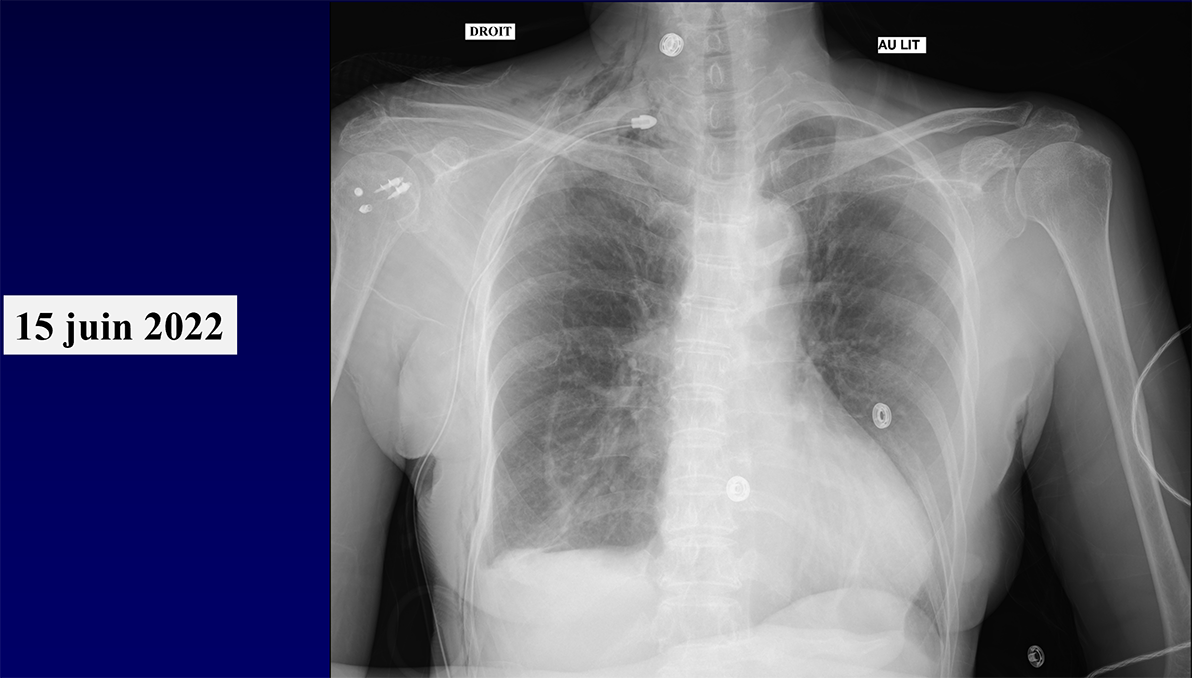

QUIZ N° 013*

Homme de 70 ans

QUEL EST VOTRE DIAGNOSTIC ?

Quel est le mécanisme le plus probable de cette pathologie ?